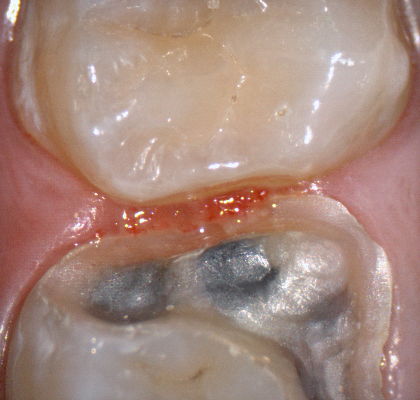

The following pictures depict the sequence of burs we recommend that you use to finish a preparation quickly. While patient is getting numb, take a quick look at the clearance you will need to reach proper material thickness. Once the quadrant is isolated with isolite and optragate, take an occlusal router bur and create a trough to gain the proper depth. Follow that with a flat disk, and you can quickly reduce the occlusal height.

A shoulder bur of .8 mm thickness can help you reduce the interproximal areas as well as the buccal and lingual margin lines. Before finishing the prep, place hemostatic agent like expasyl in the sulcus and place retraction cord. while it is setting, check your reduction. If you need more space, now is the time to reduce some more.